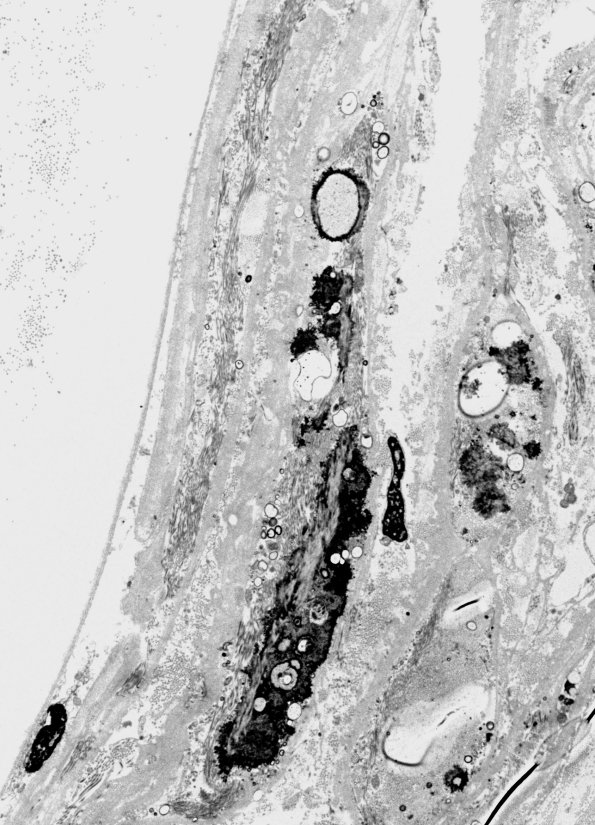

6B1-3 The perineurium exhibits numerous foci of calcifications, which are not accompanied by macrophages or inflammatory cells. (electron micrographs)